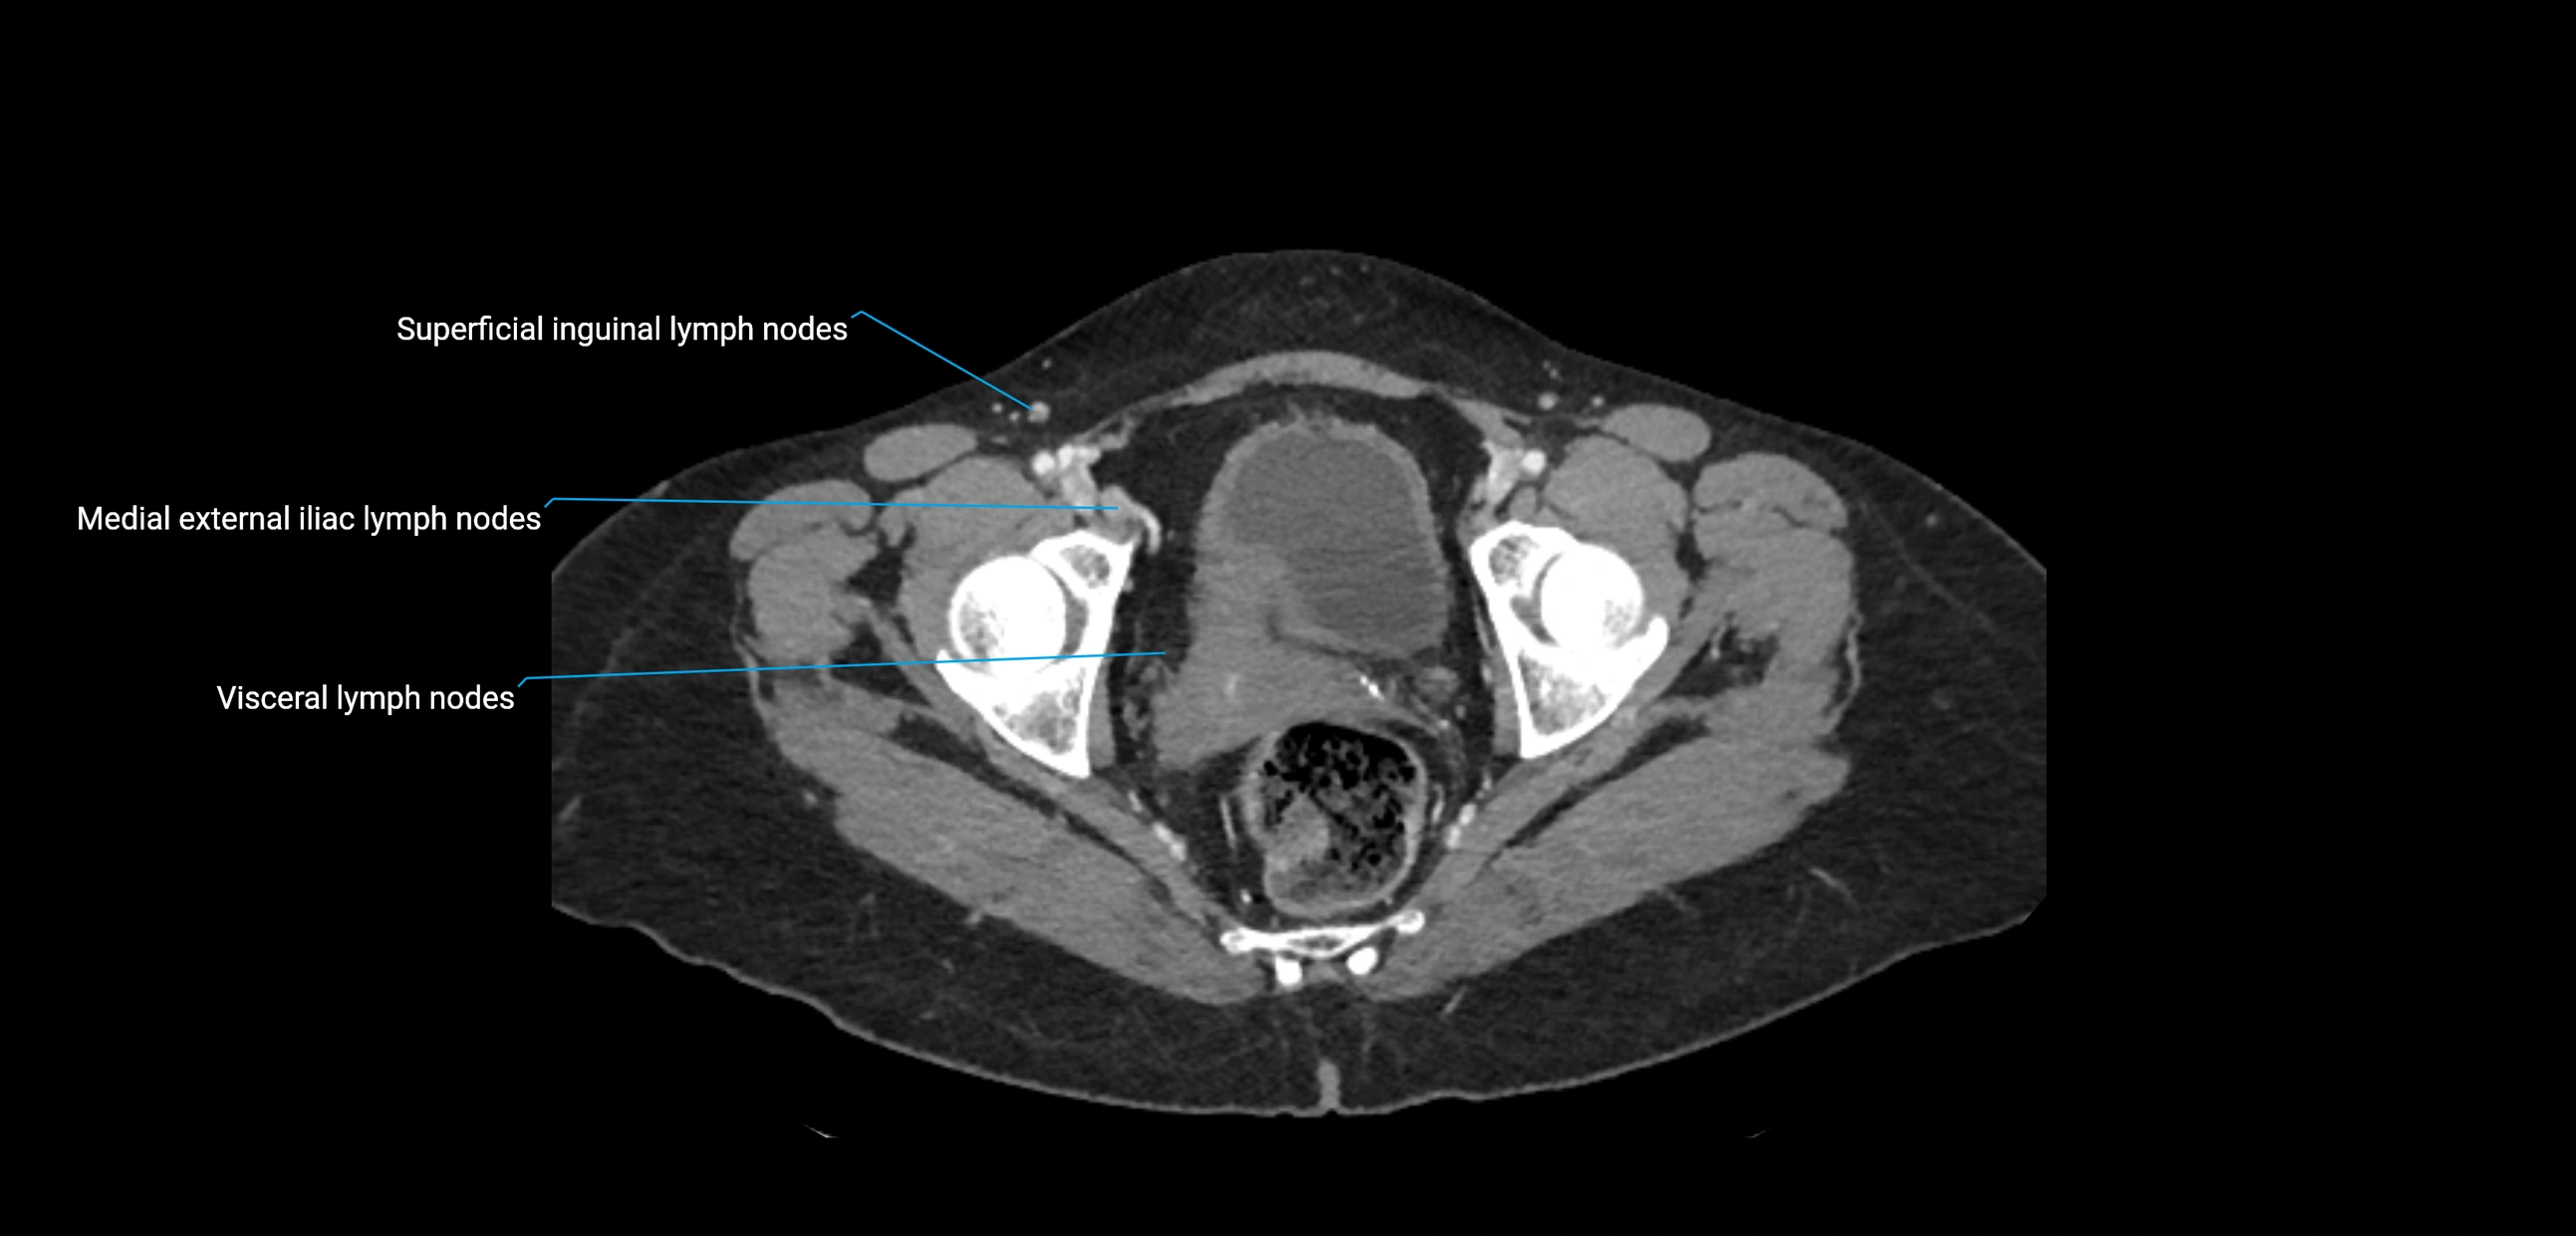

These nodes receive lymph from a wide range of abdominal and pelvic structures. Specifically, they drain lymph from the kidneys, suprarenal glands, gonads (testes/ovaries), uterus, uterine tubes, and pelvic organs, before converging into the lumbar lymphatic trunks, which terminate in the cisterna chyli → thoracic duct.

Clinically, the lateral aortic lymph nodes are critically important in oncology, being involved in the spread of testicular cancer, ovarian cancer, endometrial cancer, cervical cancer, renal malignancies, and retroperitoneal lymphomas. They are also key targets in retroperitoneal lymph node dissection (RPLND) for testicular tumors.

CT Appearance

CT Pre-Contrast:

• Nodes appear as soft-tissue density nodules adjacent to the aorta and IVC

• Calcification may be seen in chronic infections (e.g., tuberculosis)

CT Post-Contrast:

• Normal nodes enhance homogeneously

• Malignant nodes may show heterogeneous enhancement, central necrosis, or conglomerate formation

• Size >1 cm short axis is suspicious, though morphology and distribution are equally important